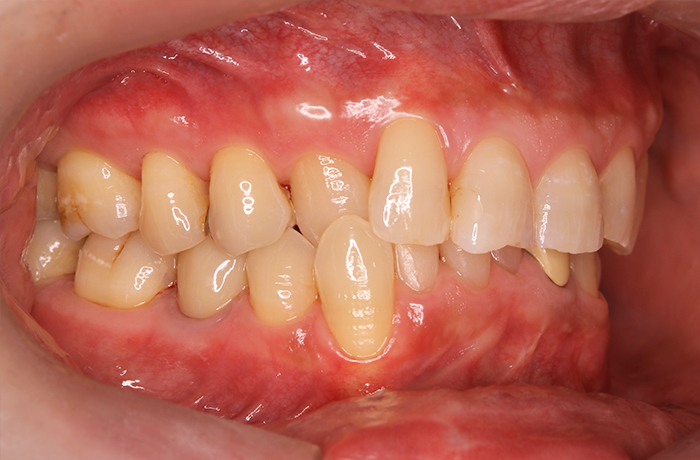

治療後

治療終了後の完成した口腔内と

レントゲン写真

サイナスリフト部の骨再生は良好で、インプラントの安定性も高く、骨吸収や透過像はありませんでした。

最終補綴装着後は咬合バランスが改善し、良好な咀嚼機能が回復。審美性にも優れ、患者様にもご満足いただけました。